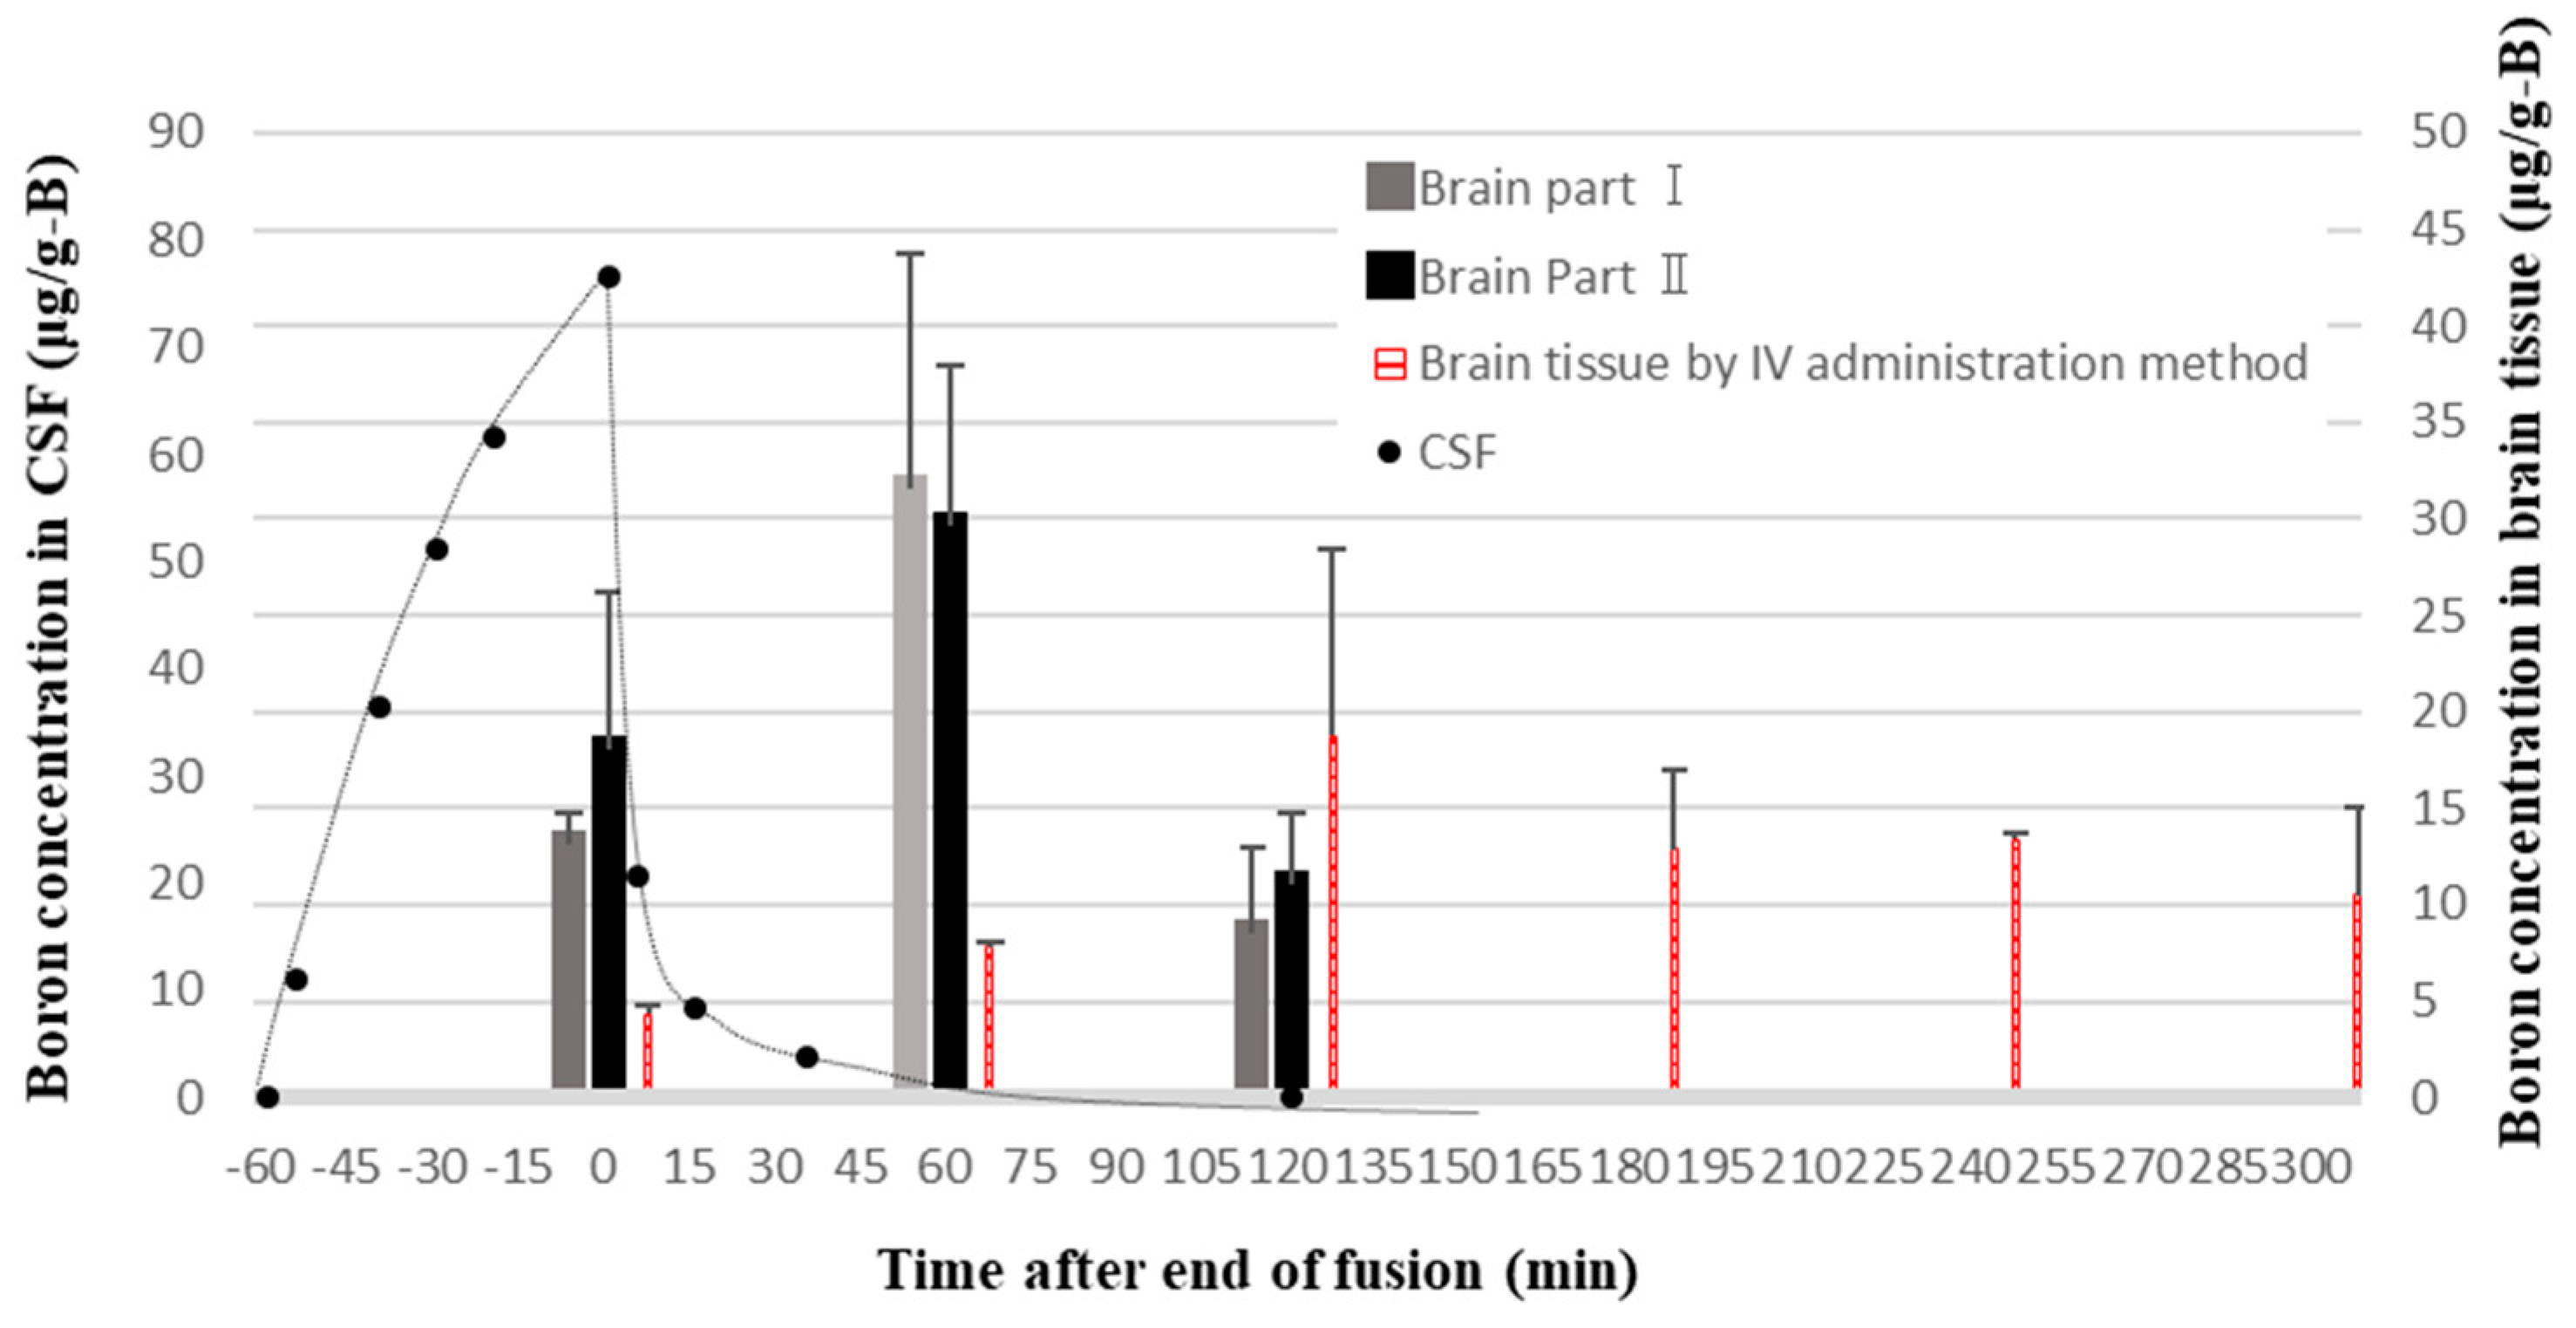

2.5. Boron Concentrations in Various Normal Tissues of Rat Heads Administered BPA via Both the CSF and IV Methods

4.2. Boron Concentration in Normal Tissues and the T/N Ratio in BNCT

4.3. BPA Pharmacokinetics and Pharmacodynamics in Brain Tissue